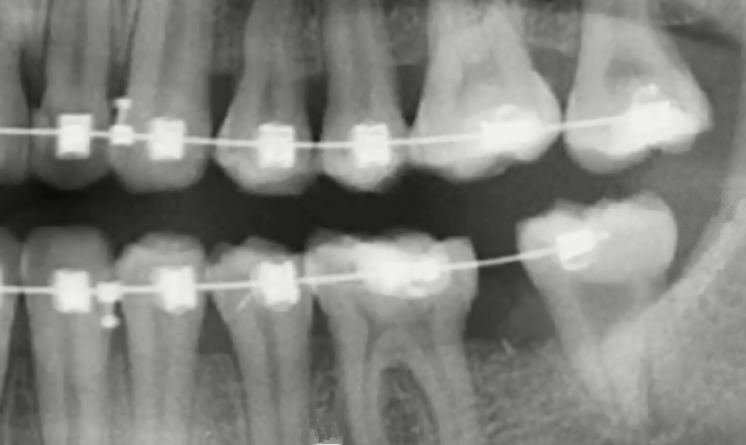

正畸把智齒成功牽引出來